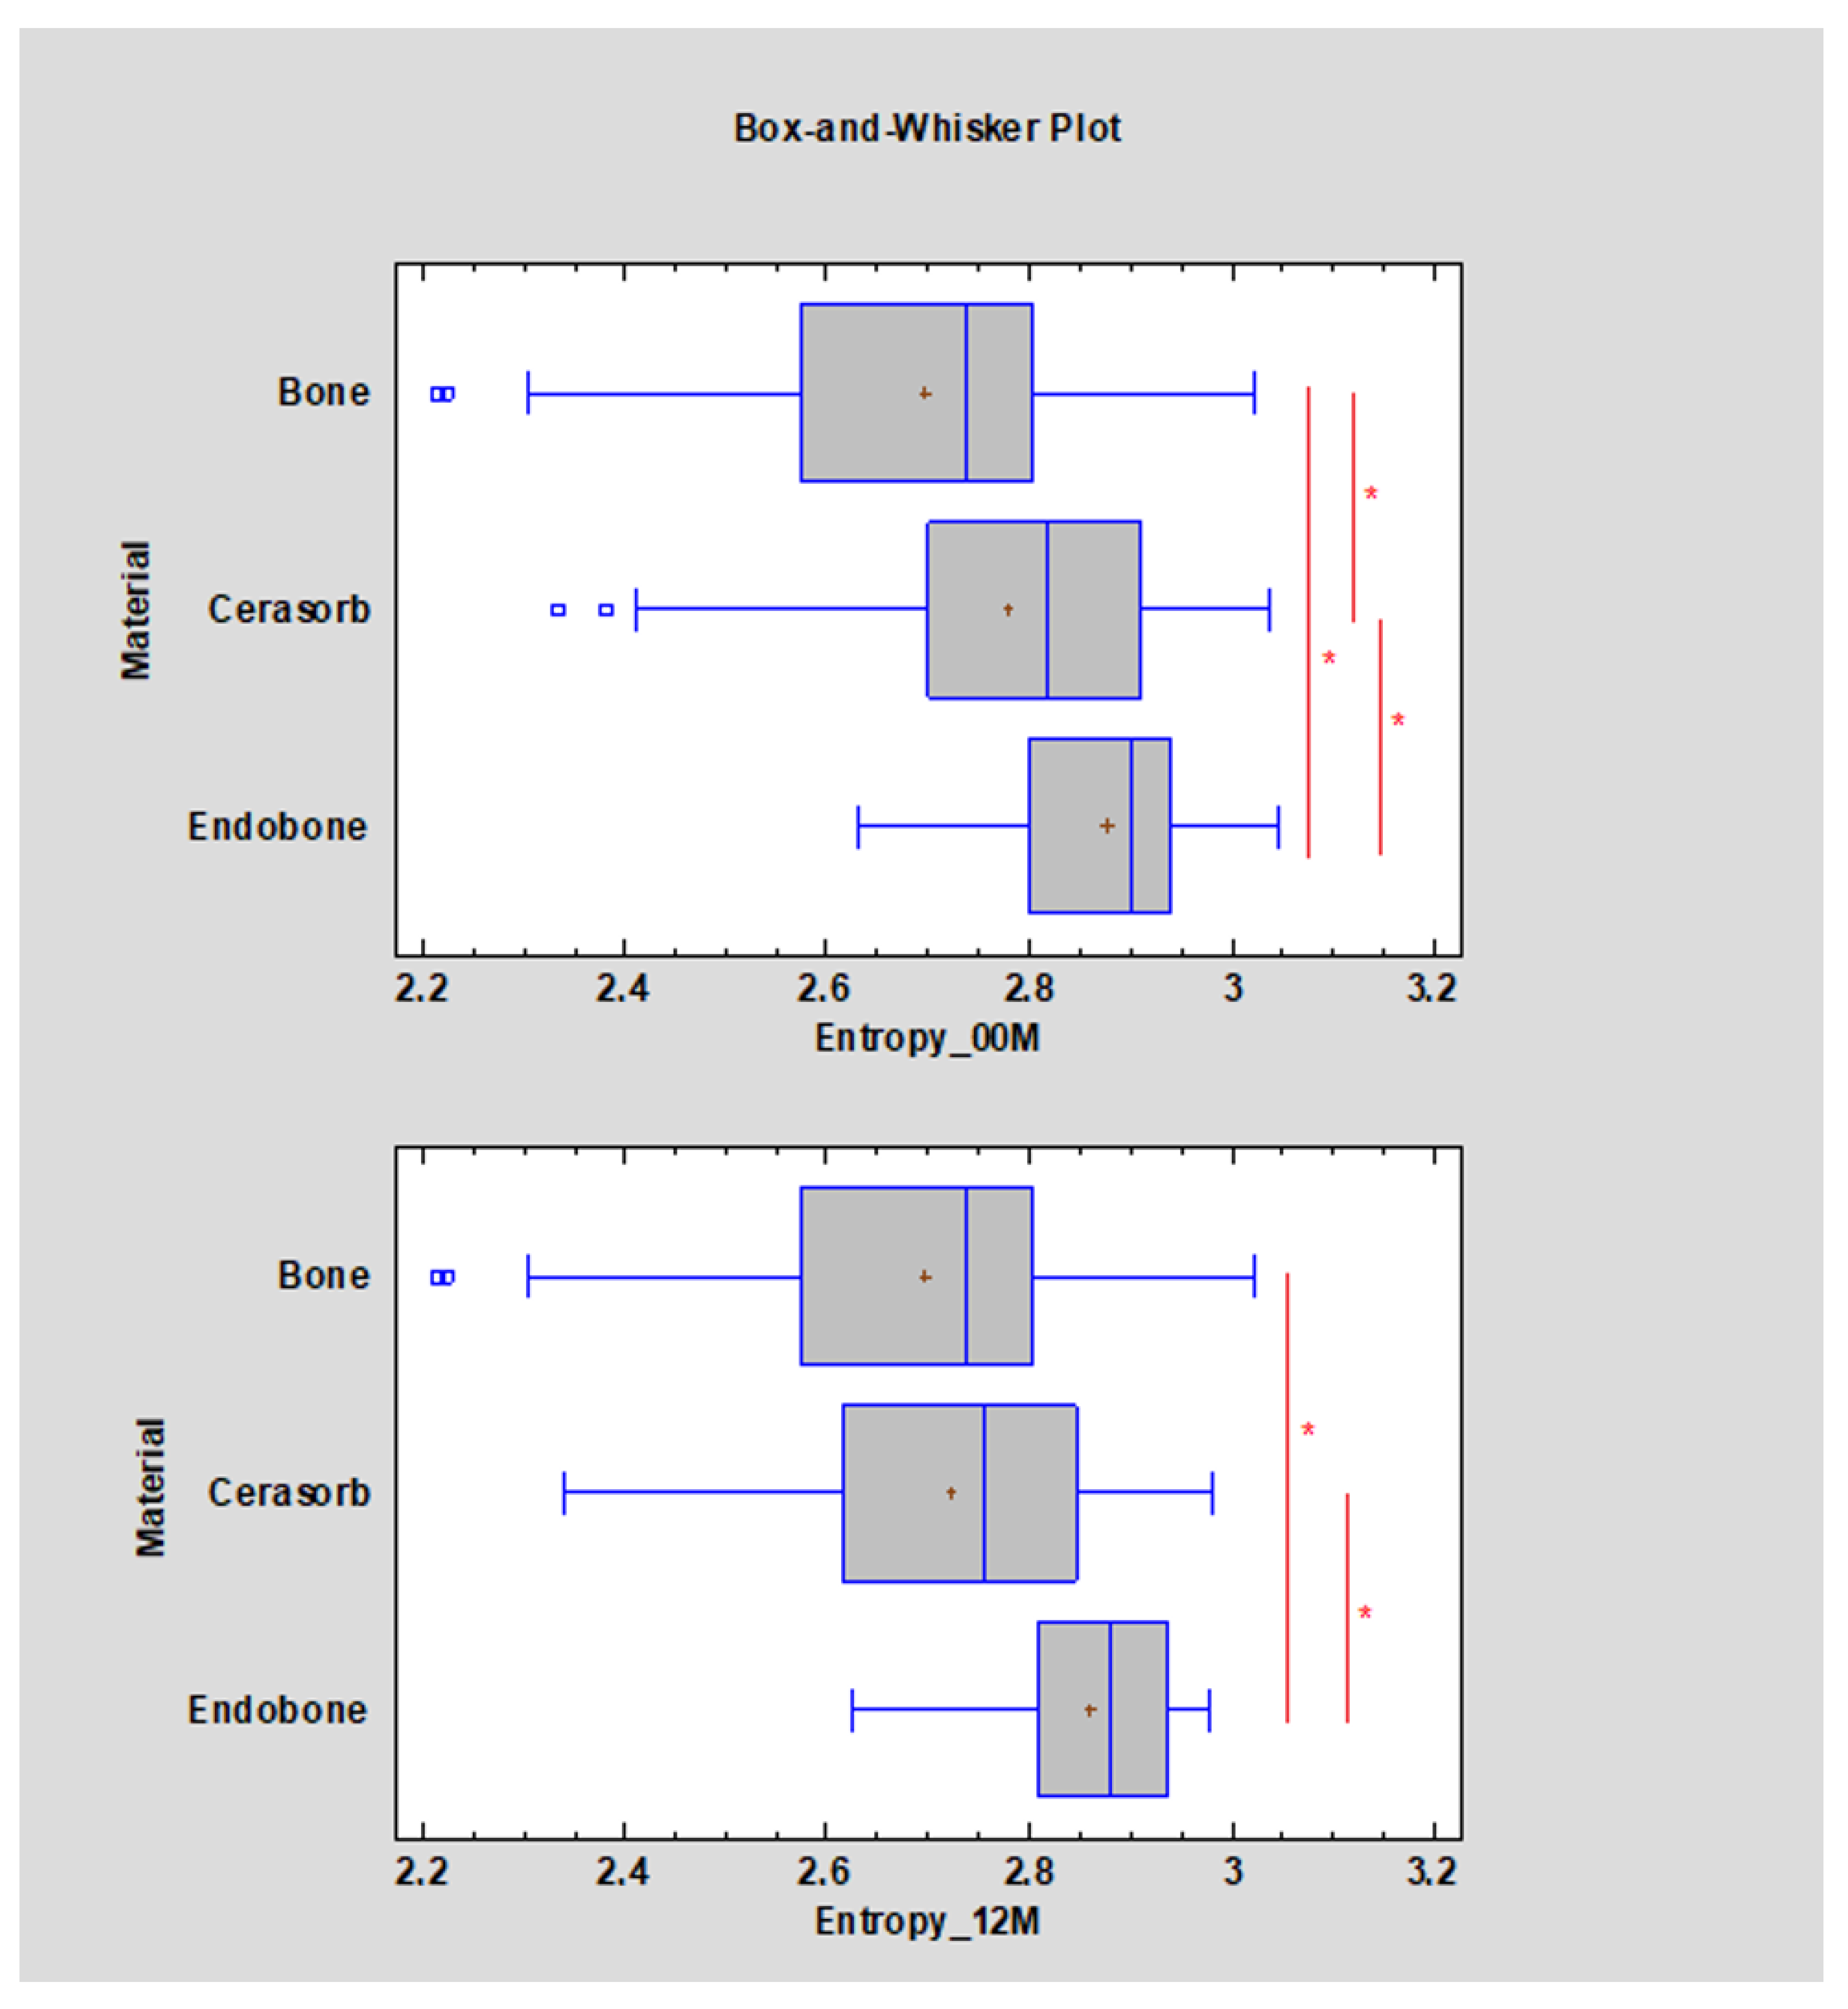

3. Results

- Sum average;

- Entropy